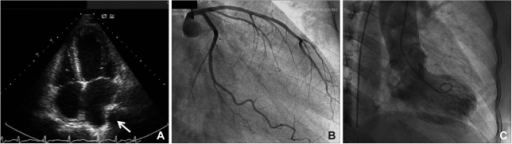

What's the Diagnosis?